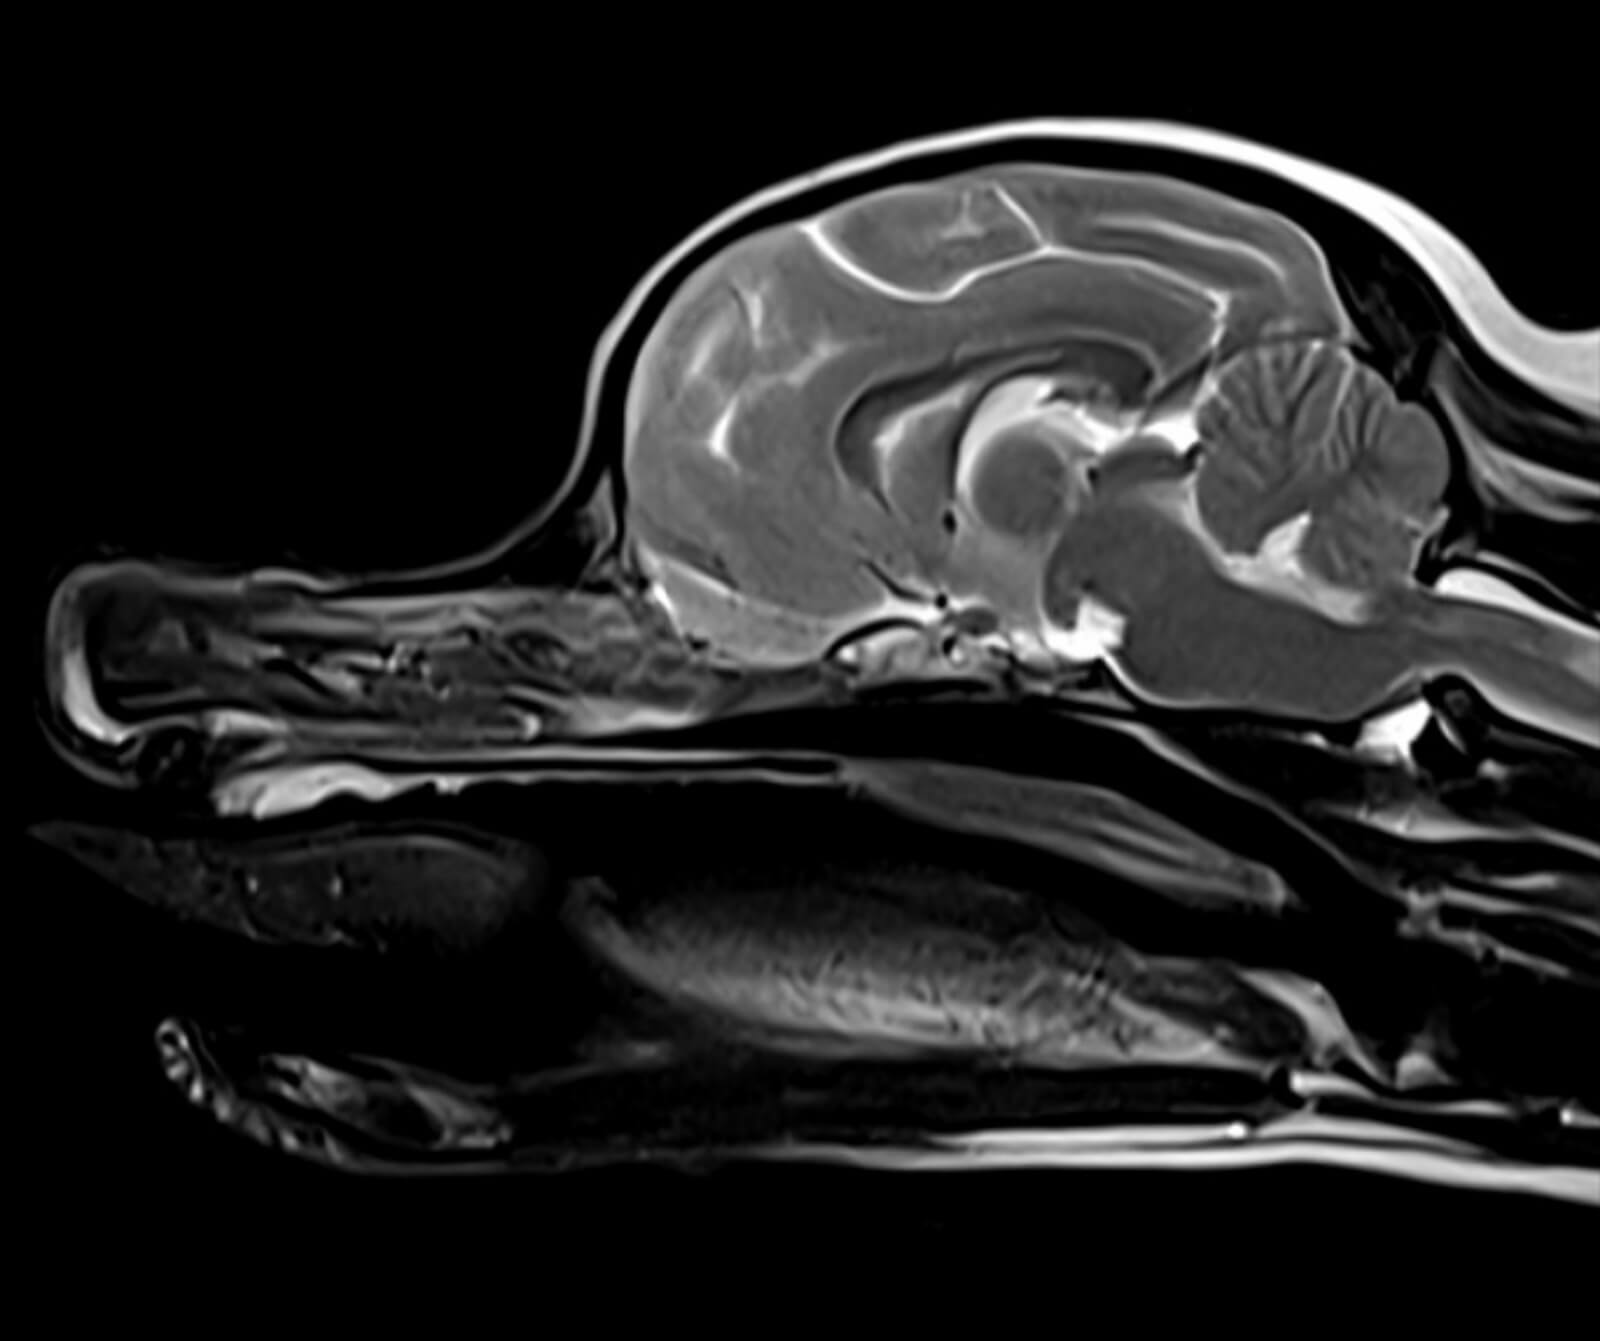

Manyetik Rezonans Görüntüleme (MR), sevimli dostlarımızın vücudundaki doku ve organların yüksek çözünürlükte, ayrıntılı ve güvenli biçimde değerlendirilmesini sağlayan ileri düzey bir tanısal görüntüleme yöntemidir. Radyasyon içermeyen bu yöntem, özellikle yumuşak dokuların detaylı incelenmesi gereken durumlarda en değerli tanı araçlarından biridir.

Veteriner hekimliğinde MR; beyin, omurilik, sinir sistemi, kas-iskelet sistemi ve iç organ hastalıklarının değerlendirilmesinde kritik rol oynar. Kemik yapılar dâhil olmak üzere vücudun tüm bölgeleri MR ile ayrıntılı şekilde incelenebilir.

• Beyin ve nörolojik hastalıkların değerlendirilmesi

• Spinal kord incelemeleri

• Tümörler, felç, beyin kanamaları ve damar tıkanıklıkları